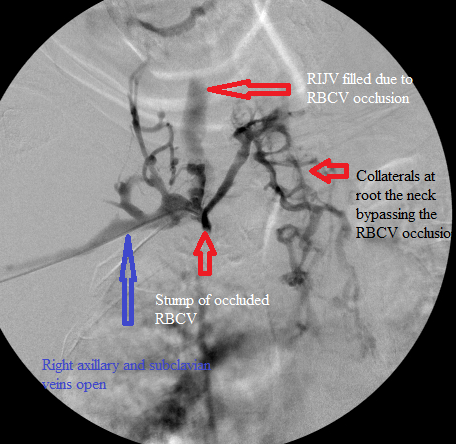

RBCV occlusion and collaterals at root of neck

Central venogram. Note numerous collaterals bypassing the occluded RBCV.